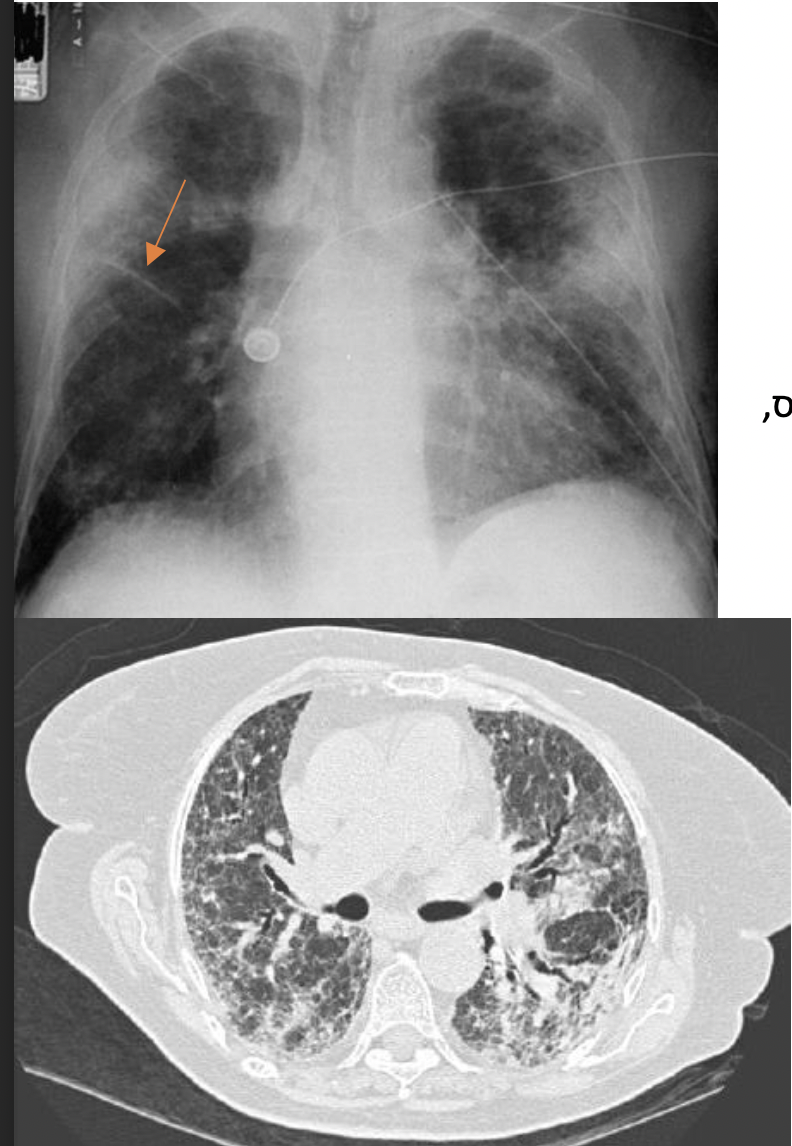

IPF – Idiopathic Pulmonary Fibrosis מה המאפיינים של?

תת סוג של מחלות פרנכימטיות שמאופיין בפרוגנוזה גרועה ותגובה לא טובה לטיפולים. לא יודעים מה הסיבה- אדיופתי.

גברים, 50+, מעשנים, עם ריפלוקס, לאחר חשיפה לאזבסט.

בתחילה תהיה דיספניה במאמץ ושיעול יבש, בהמשך דיספניה במנוחה ושיעול ליחתי- הליחה לא יכולה להתפנות מדרכי האוויר עקב הצלקות (ברונכיאקטזיה).

סיטי עוזר לאבחן ולא תמיד צריך ביופסיה.

honey comb יש

סיטי וביופסיה יהיו הטרוגניים- אזורים בריאים לצד חולים. לא נראה תאי דלקת.

בביופסיה סיבי קולגן ייצבעו בכחול (בחץ)

טיפול- הפסקת עישון וחשיפה לאלרגנים, טיפול ברפלוקס, תרופות אנטיפיברוטיות. סטואידים לא יעזרו כי המחלה לא דלקתית.